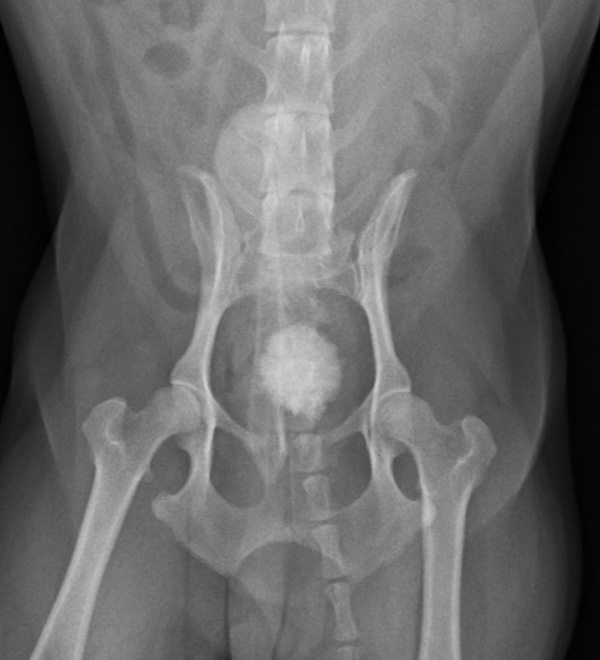

血尿、頻尿の症状で来院されました。レントゲン・超音波検査にて、膀胱内に結石を認め、手術による摘出となりました。無事手術も終わり元気に退院しました。よかったね。